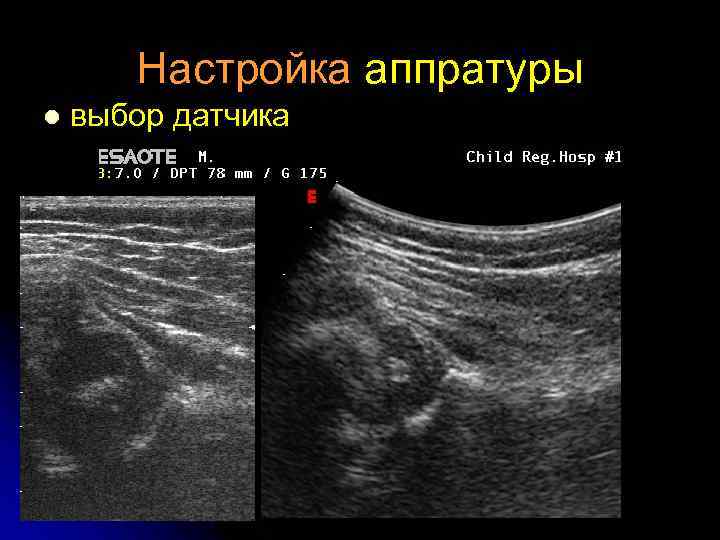

Техника l l l Частота 7 -10 МГц Настройка аппратуры: - интенсивность ультразвука - выравнивание глубины - контрастность - «близкий фокус» - пре- и постпроцессинг Измерения проводятся на бумаге или при помощи меню Масштаб ≥ 1: 1, 7 Осмотр справа и слева обязателен

Настройка аппратуры l - интенсивность ультразвука

Настройка аппратуры l выбор датчика

Настройка аппратуры l Глубина сканирования

Настройка аппратуры l контрастность

Настройка аппратуры l пре- и постпроцессинг